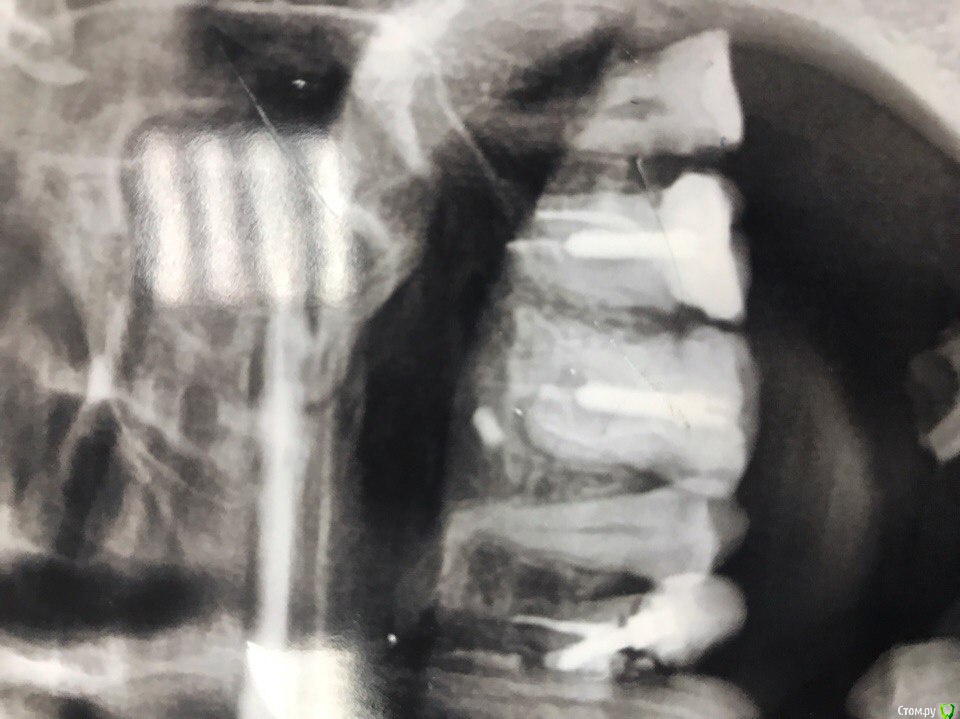

Ульяна 1980 Опубликовано 1 марта, 2017 Поделиться Опубликовано 1 марта, 2017 Добрый день, на снимке обнаружили инородное тело, в области шестого зуба, не могут понять что это, то ли корешок отломился от другого зуба и переместился, то ли это лекарство из канала) А главное меня беспокоит вопрос: Что делать? Как его достать? Если вдруг это обломок корня, то сказали что даст воспаление. Если это лекарство, понимаю, что ничего страшного? Благодарна, за любое мнение) Ссылка на комментарий

АнтонТЛТ Опубликовано 1 марта, 2017 Поделиться Опубликовано 1 марта, 2017 Не корень 2 Ссылка на комментарий